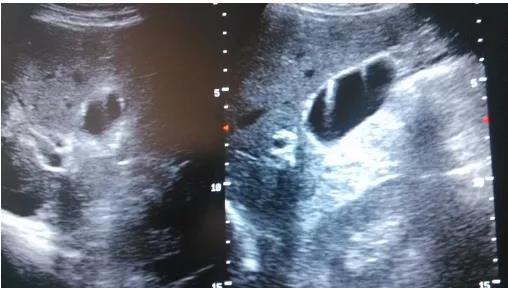

# 息肉大小怎么看?#